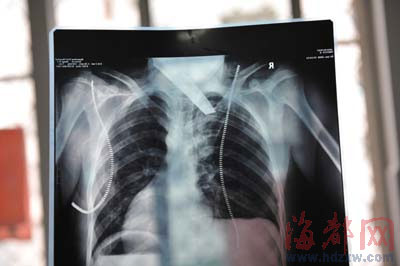

前晚,在第一醫(yī)院急救室,經(jīng)過4個(gè)多小時(shí)的搶救,醫(yī)生將匕首從小勇身上取出,發(fā)現(xiàn)這把匕首的刀尖扎斷了1厘米。由于小勇肺部被刺中,昨天上午,醫(yī)生再次進(jìn)行了3個(gè)多小時(shí)的手術(shù),切除了受傷的部分肺,直到下午,小勇才挺過來。“挺了一夜,現(xiàn)在總算醒了過來。”楊女士一夜沒睡,守在手術(shù)室外7個(gè)多小時(shí),生怕兒子再醒不過來。不過,由于傷勢(shì)嚴(yán)重,小勇目前戴著氧氣呼吸,仍未脫險(xiǎn)。